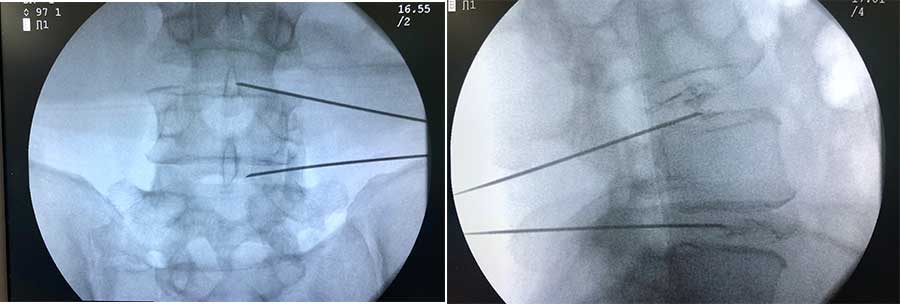

- Myelogram or CT Myelography (CT): A contrast agent is used to visualize the spinal cord and spinal nerves. It may provide detailed information on the herniated disk but it is considered an invasive examination.

In lumbar microdiscectomy, a small portion of the bone is excised above the nerve root along with much of the disc material that presses and irritates it, providing more space. Through a small incision, a “window” opens to the spine about three by four inches in diameter. Anything that can cause compressive effects on the nerve root is removed through this space.

- A small incision is performed about 3-4 cm in the midline of the spine at the height of the disc in the lumbar spine.

- The erector spinae are lifted and removed from the lamina of the vertebra. Since these muscles are vertical, it is recommended that they are removed and not intersected.

- The surgeon enters the spinal cord by removing a small portion of the ligamentum flavum. With the help of a surgical microscope, the surgeon can remove all those tissues (osteophytes, disc material) around the nerve root.

- Often a small part of the facet joint is removed to facilitate access to the nerve root and to increase the space around the nerve.

- The nerve root is then moved away with subtle manipulations and the disc material that puts pressure on it is removed.